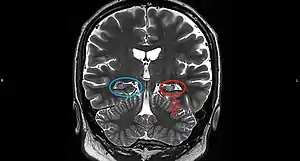

| Mesial temporal sclerosis (MTS) | |

On a MRI T2-weighted or T2–fluid‐attenuated inversion recovery (FLAIR) scan, hippocampal sclerosis appears as an increased signal, smaller sized (atrophic) hippocampus with a less well-defined internal structure.[2] Increased signal means that hippocampal sclerosis will appear brighter on the MRI image. Less well-defined internal structure means the expected sharp boundaries between hippocampal gray and white matter structures are absent.[2] The total volume of the hippocampus is also reduced.[2] The reduced volume arises from neuronal cell loss, and increased signal arises from gliosis.[2]